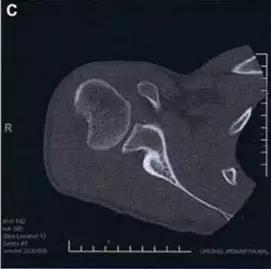

1. 三平面骨折(Triplane fracture )

即累及远端胫骨骨骺的骨折可因骨折线延入其他两个平面而变得复杂,因而称之。骨折由矢状面内的骨骺骨折,经生长板外侧面的轴位面内水平方向骨折,与冠状面内经干骺端到骨干的斜行骨折,自生长板的前侧面伸延至胫骨的后侧皮质。

三平面骨折 CT 片

三平面骨折 CT 重建